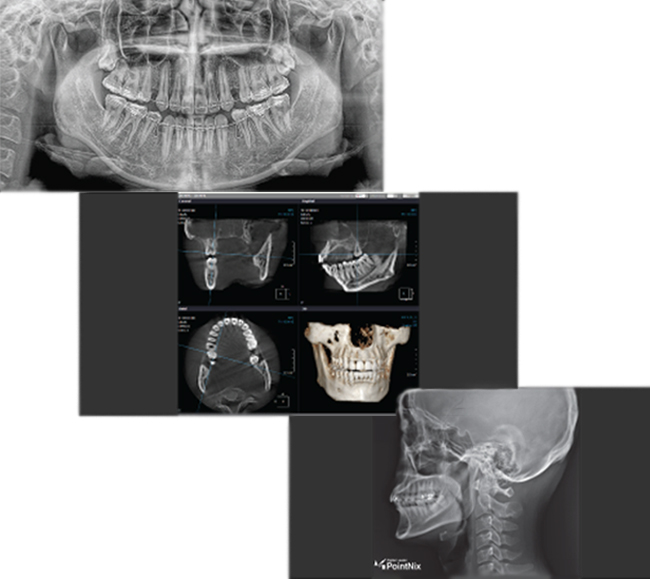

Показания к выполнению дентальной компьютерной 3D томографии: определение состояния корней зубов и окружающих их тканей, выявление скрытых кариозных полостей, травмы челюстей и повреждения зубов, различные аномалии развития и положения зубов в челюстном ряду, заболевания шейного отдела позвоночника, заболевания верхнечелюстных пазух, новообразования костей челюстно-лицевой области.